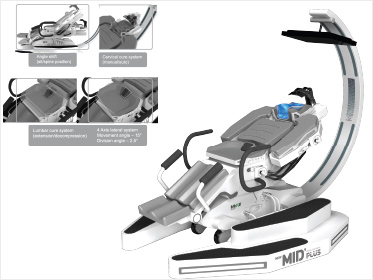

CPM

���, ���� ���� �� CPM��⸦ ���� ���������� ������������ ȸ��

CPM ġ�� Ư¡

������ ���� ���� �� ������� ���������� ȸ�������ָ� �������� ��� ���Ͽ� ������ �ּ�ȭ�Ͽ� ����Ⱓ�� �����ŵ�ϴ�.

���� �� ����ȯ�� ��������� ��Ȱ�� �̷�������� �����ָ� ���� ���������� ����� ������ �� �Ӹ� �ƴ϶� ���������� ������� �������� �ݴϴ�.

���� �� ����ȯ�� ��������� ��Ȱ�� �̷�������� �����ָ� ���� ���������� ����� ������ �� �Ӹ� �ƴ϶� ���������� ������� �������� �ݴϴ�.

CPM ġ�� ���

�����ܰ� ���� ��, ������ ���� �� ����, ������������ ������ ������ ȯ�ں�, ġ�� ��������� ����� �������� ���õ� ����ΰ����� ġȯ��, ���������, ���� �����δ� ��Ǽ� �� ġ������ �˴ϴ�.

CPM ġ�� ���

���� �� ���� 2~3�� ���� ���� ������ CPM��� �÷�����, ������ ���� �������� �ݺ� �����մϴ�. ������ ������ ���� �ʴ� ������ ���������� ������ ������ ������ ������ŵ�ϴ�.